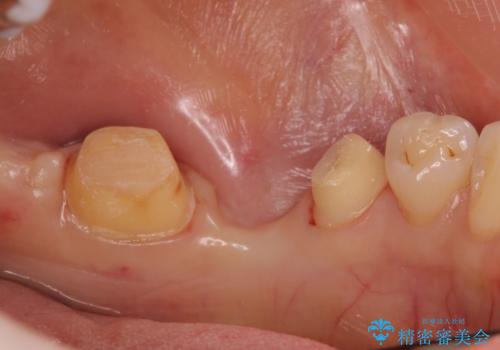

- 左下の銀歯の状態が悪く抜歯してブリッジにした患者様です。

抜歯してからブリッジの仮歯をすぐ入れるため、歯がない期間はほとんどありません。

途中全体矯正をはさみ、根の向きが並行になった状態でブリッジを入れることができました。